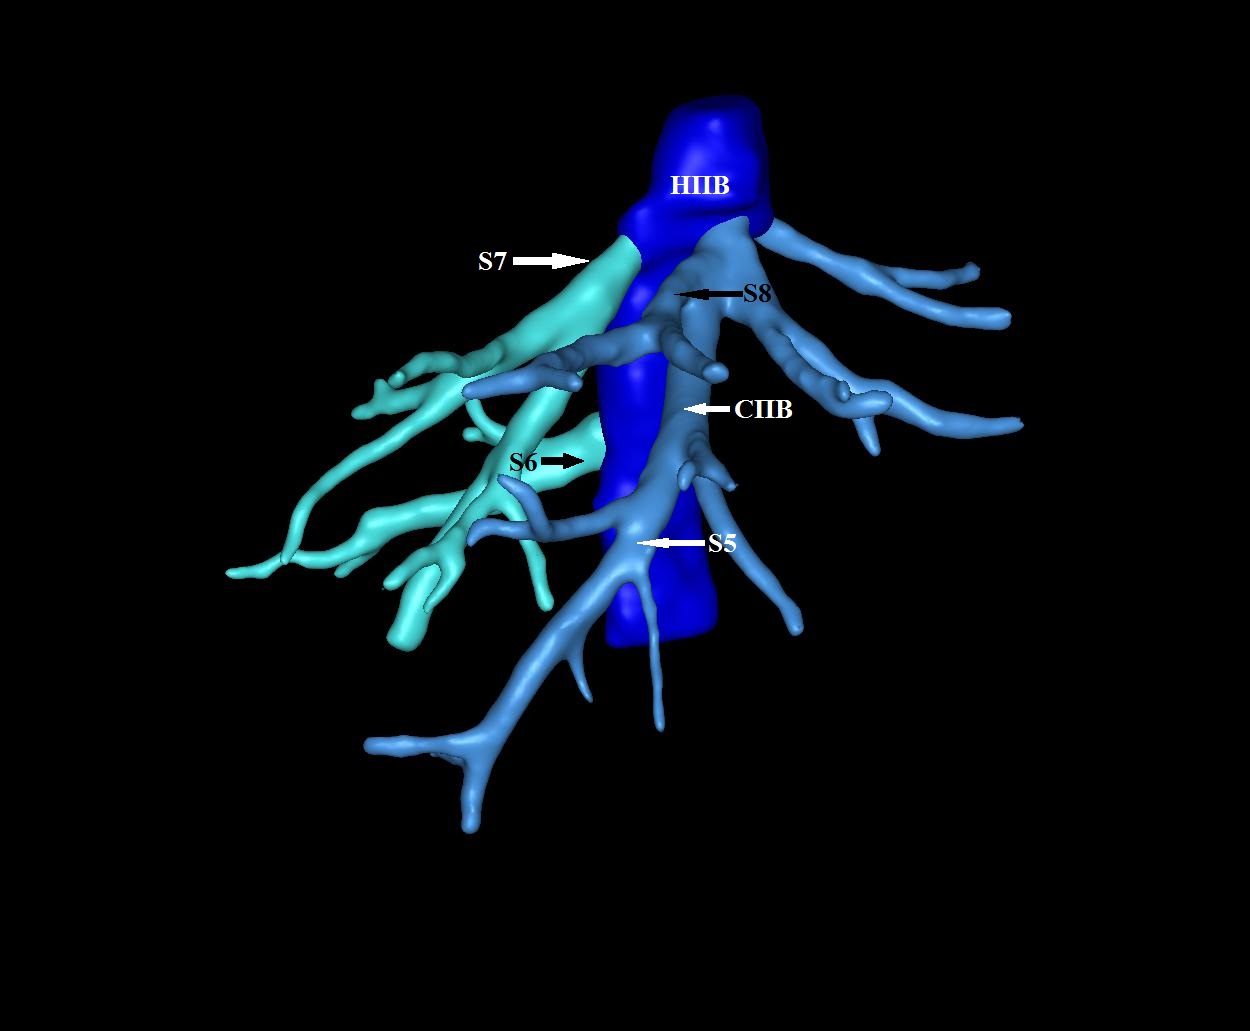

Результаты. Выявлено 14 подтипов анатомии эфферентных сосудов. Их классифицировали в 3 типа в зависимости от вклада срединной вены в отток крови от правой доли печени: кавальный (67,3%), кава-срединный (полусепаратный, 29%) и сепаратный (3,6%).

2. Тип А (схема). | |

| Тема | ||

| Тип | Исследовательские инструменты | |

Посмотреть

(1MB)

|

Метаданные ▾ | |